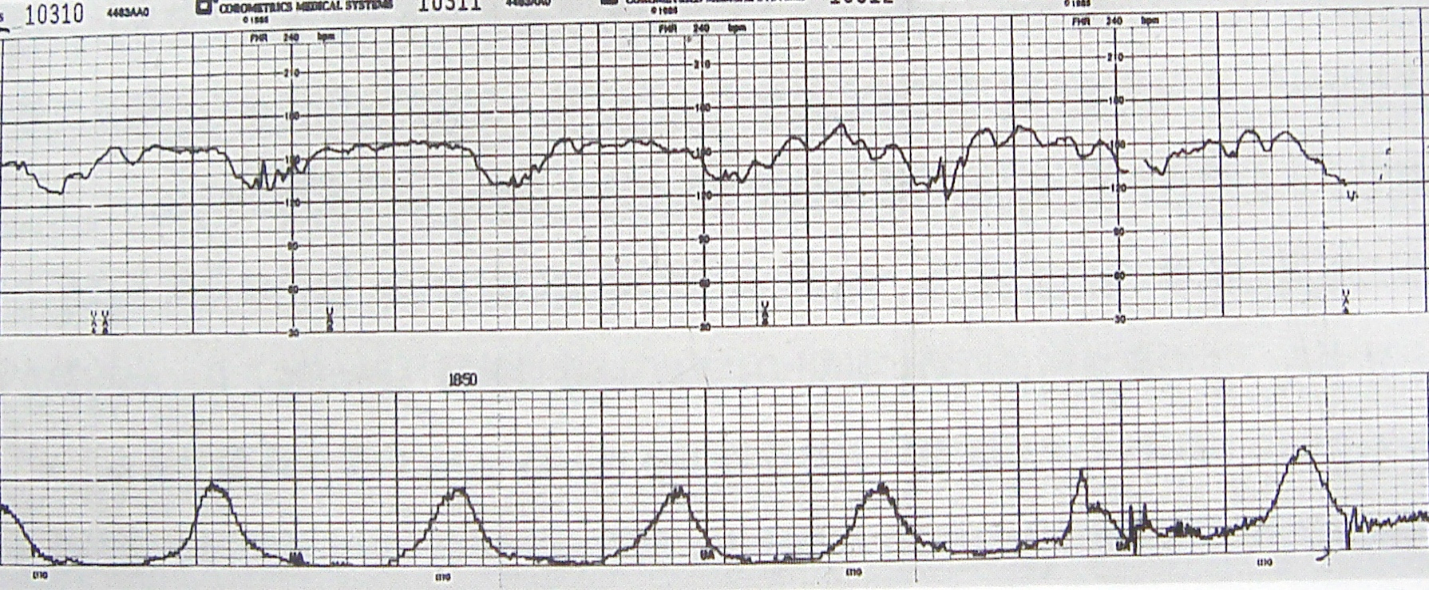

• 5.4 NST&OCT

高危妊娠监护